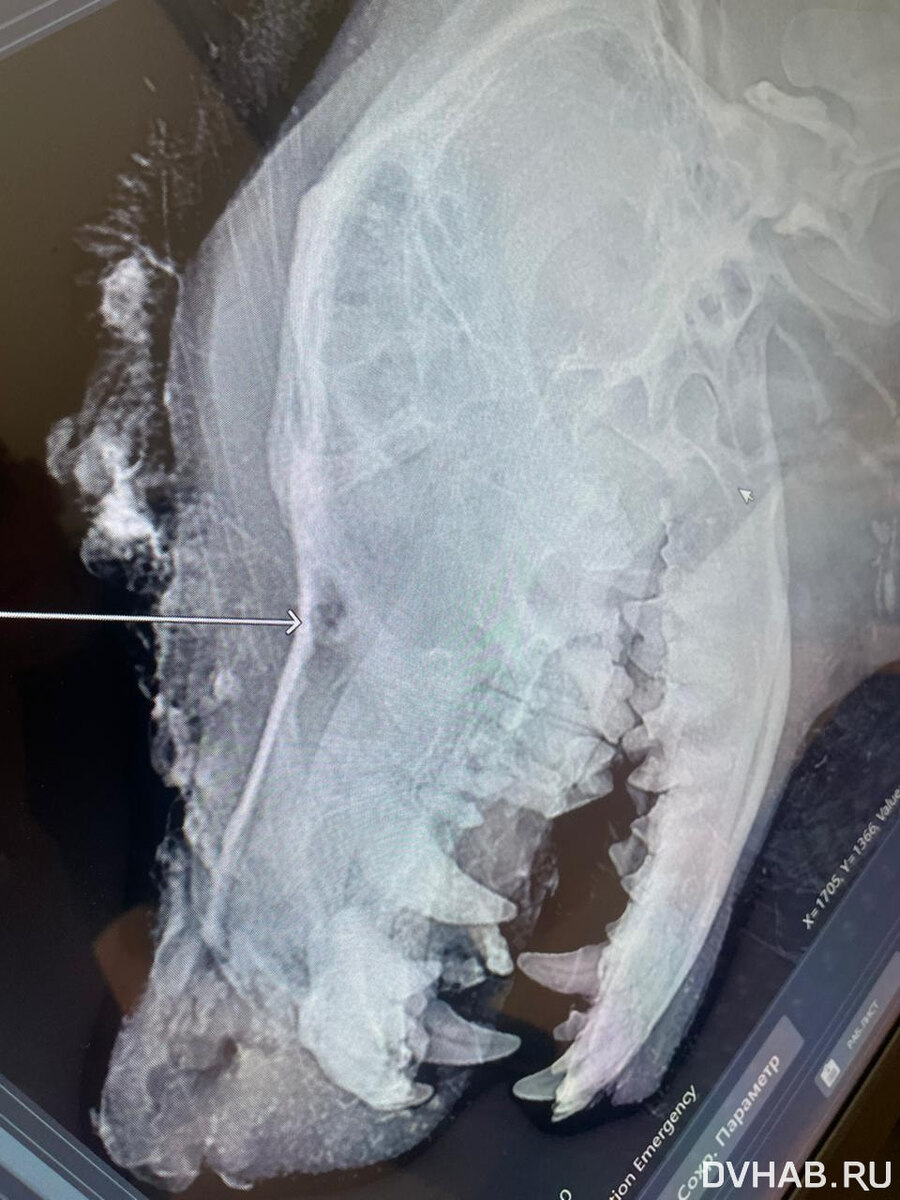

По словам врача, который осматривал животное, в собаку стреляли. Сквозная рана проходит у нее от носа до неба.